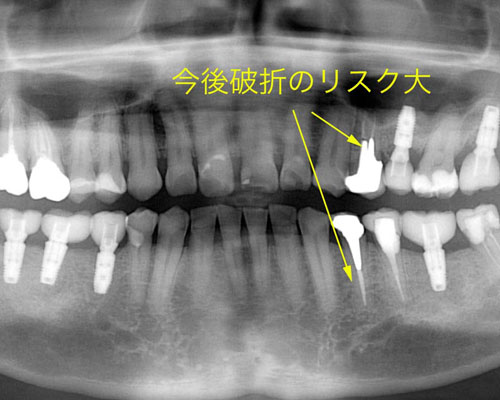

そして、とうとう右下の3番目にインプラントを入れご覧のような状態に落ち着きました。しかし、私の診断では左側の上下2本に破折のリスクがあると説明していました。するとすぐに左下の奥から4番目が一部破折を認め作り直しとなりました。